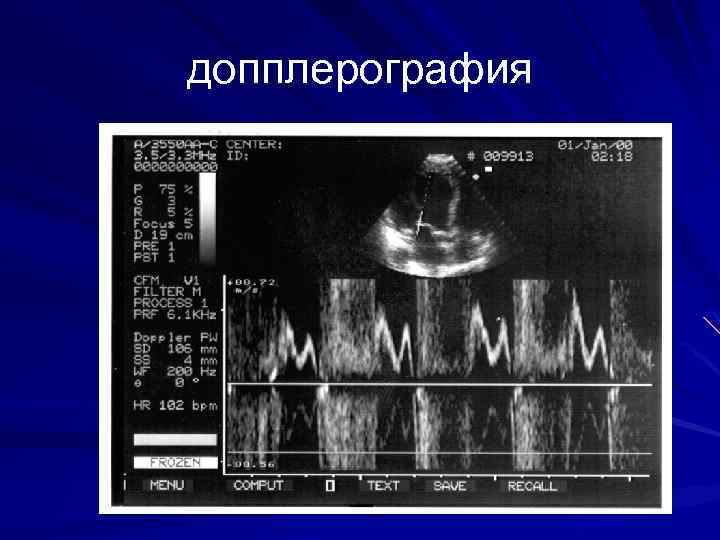

Эхокг в допплеровском режиме

допплерография

Диастолическая дисфункция при СН Норма Е >А Классический тип диастолической дисфункции Е < А Псевдонормальный тип диастолической дисфункции Е >А в 2 раза Е – скорость раннего диастолического наполнения А – скорость позднего диастолического наполнения